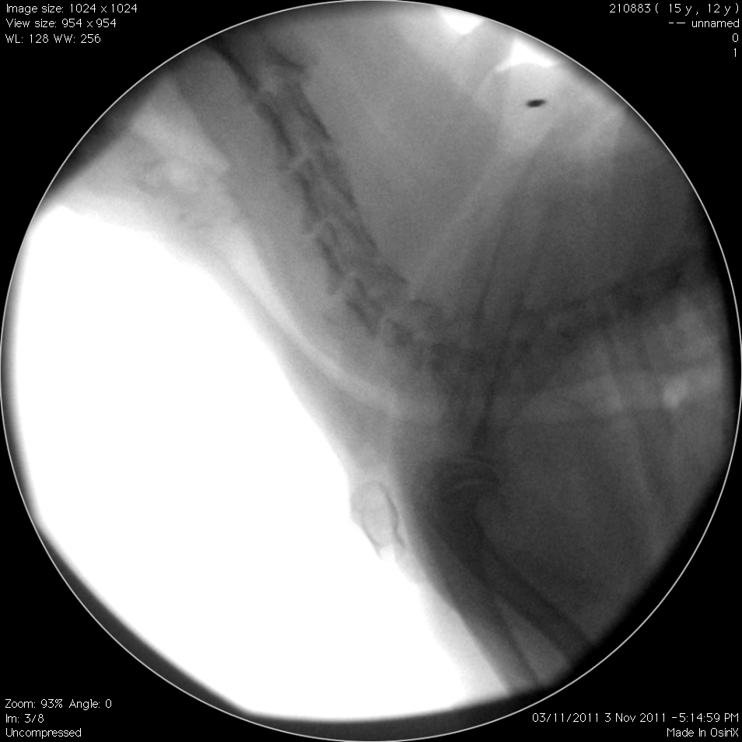

What is this and what is it useul for?

Fluoroscopy

Bone is black and air is white

Real time radiography

Tracheal diameter changes in respiratory cycle – good for tracheal collapse